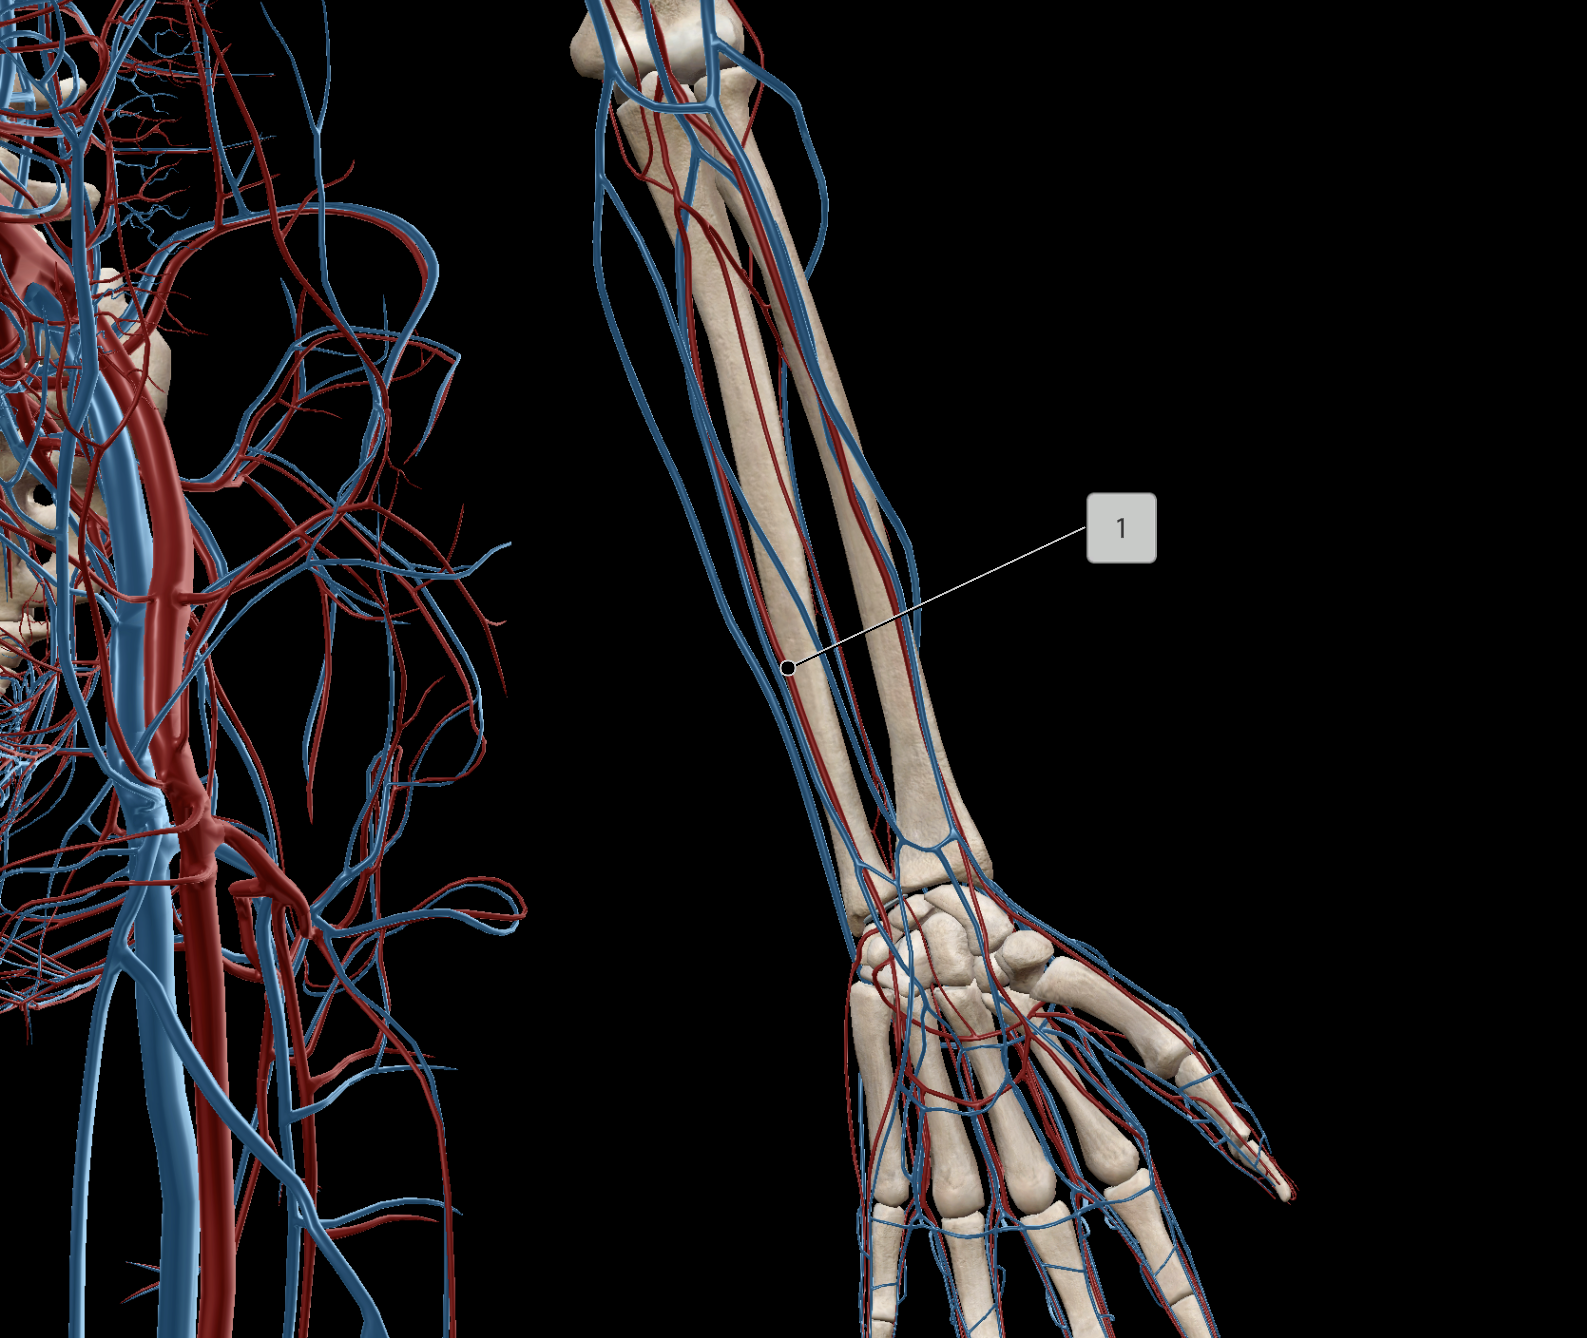

Brachial Artery

Ulnar Artery

Radial Artery

Brachial Vein

Radial Vein

Ulnar Vein